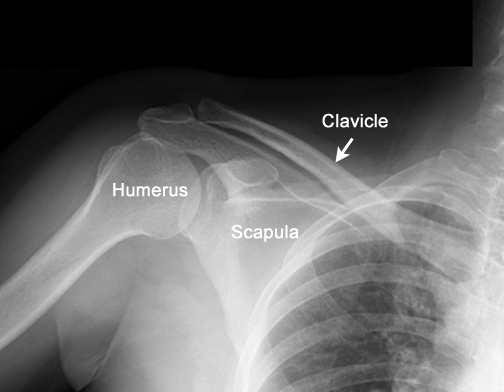

Identify the clavicle. Click the image for labeling.